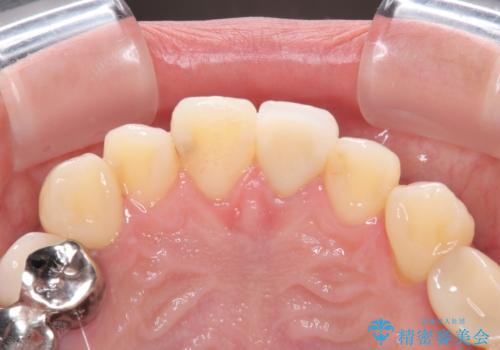

- 以前保険診療で行った前歯を自然できれいなセラミックにしたいと来院された患者様です。

古い材料と虫歯を除去して、土台の形を整え、より自然なオールセラミッククラウンにすることとしました。